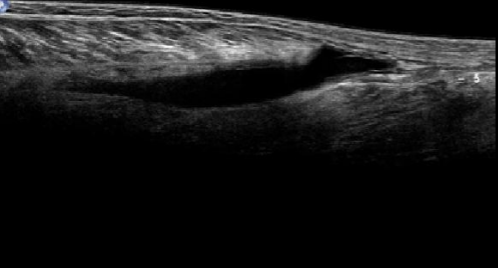

A

Normal

Deltoides

Bursa

Supraespinoso

Cartilago

Humero